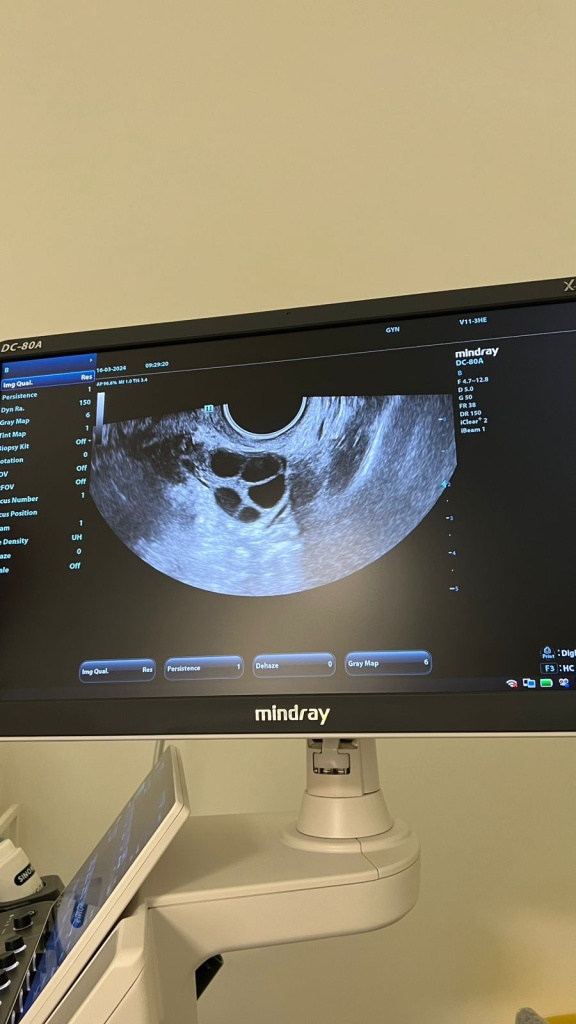

В первый день нового цикла я сдала кровь и сделала УЗИ, а уже на второй день начала уколы для стимуляции фолликулов. Фолликулы — это маленькие «пузырьки» в яичниках, где растут яйцеклетки. Обычно каждый месяц созревает только один, но под действием гормонов — сразу несколько. Чем их больше созреет, тем больше будущих эмбрионов получится.

Через два дня я пришла на УЗИ и увидела на экране 11 подрастающих фолликулов. И вот только в этот момент до меня дошло, какое же это чудо — из крошечной клетки может вырасти человек! Я никогда особо не думала о детях, но в тот день поймала себя на мысли: «А ведь мне было бы интересно пройти этот путь до конца». Вероятно, это во мне заговорили гормоны.